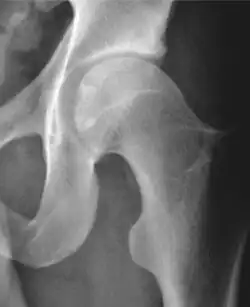

Projectional radiography ("X-ray") is often considered first line for FAI.[10] Anterior-posterior pelvis and a lateral image of the hip in question should be attained.[10] A 45-degree Dunn view is also recommended.[10][19]

| Femoral head-neck offset | ![]() |

Offset of the femoral head with regard to most prominent aspect of the femora neck | >10 mm |